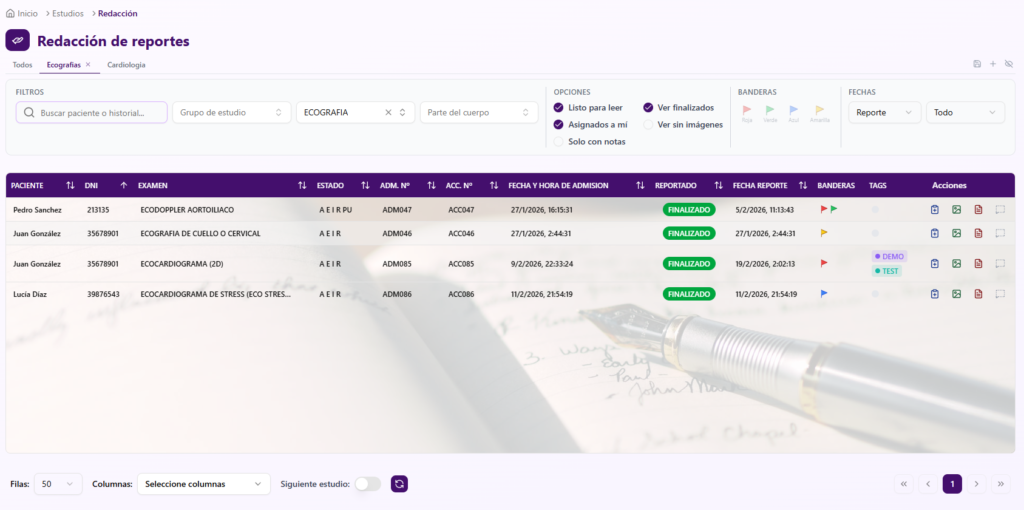

El Generador de Informes es el espacio de trabajo donde el radiólogo redacta, revisa y firma el informe. Fue diseñado para minimizar el tiempo de carga y maximizar la concentración clínica.

Firma digital y control de versiones

– Verificación de identidad con credenciales del médico al momento de firmar

– Proceso de firma digital que certifica la autoría y cierra el informe

– Posibilidad de quitar la firma antes de la distribución si se requieren correcciones

– Addendums: agregá aclaraciones o correcciones a informes ya firmados sin borrar el texto original

– Trazabilidad completa: quién firmó, cuándo y desde qué sede